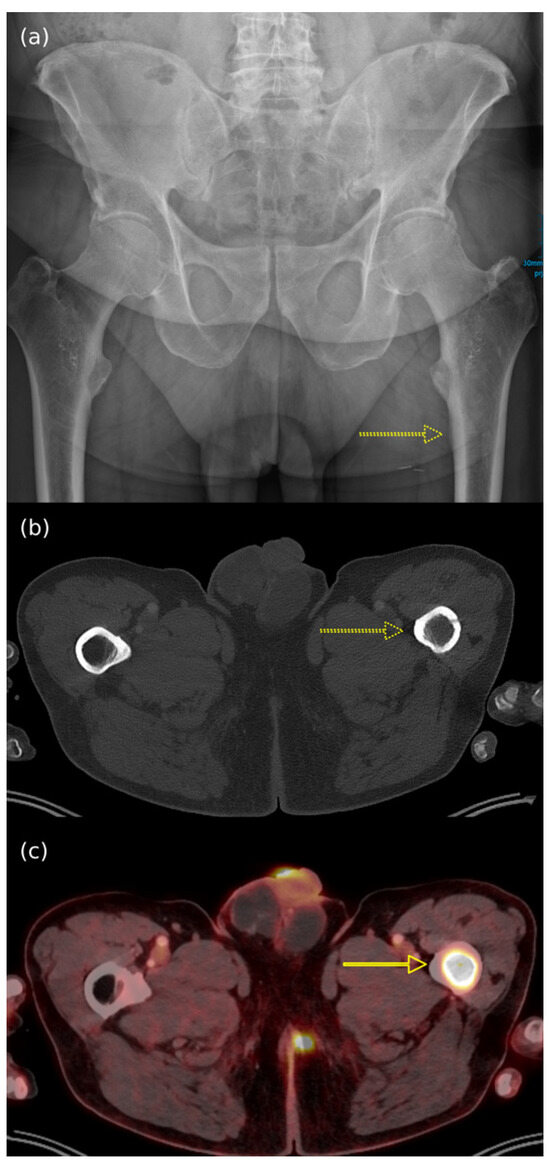

- Akaike, G.; Akaike, T.; Fadl, S.A.; Lachance, K.; Nghiem, P.; Behnia, F. Imaging of merkel cell carcinoma: What imaging experts should know. Radiographics 2019, 39, 2069–2084. [Google Scholar] [CrossRef]

- Oh, H.Y.; Kim, D.; Choi, Y.S.; Kim, E.K.; Kim, T.E. Merkel Cell Carcinoma of the Trunk: Two Case Reports and Imaging Review. J. Korean Soc. Radiol. 2023, 84, 1134–1139. [Google Scholar] [CrossRef]

- Li, X.; Wu, N.; Zhang, W.; Liu, Y.; Ming, Y. Differential diagnostic value of 18F-FDG PET/CT in osteolytic lesions. J. Bone Oncol. 2020, 24, 100302. [Google Scholar] [CrossRef]

- Patel, P.Y.; Dalal, I.; Griffith, B. [18F]FDG-PET Evaluation of Spinal Pathology in Patients in Oncology: Pearls and Pitfalls for the Neuroradiologist. American Journal of Neuroradiology. Am. J. Neuroradiol. 2022, 43, 332–340. [Google Scholar] [CrossRef]